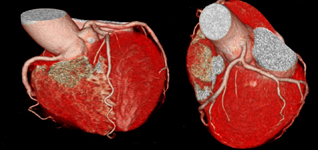

今までは心臓のCTを取ることは不可能でしたが、64スライスCTでは綺麗に撮影することができます。

冠状動脈が綺麗に見えますね。